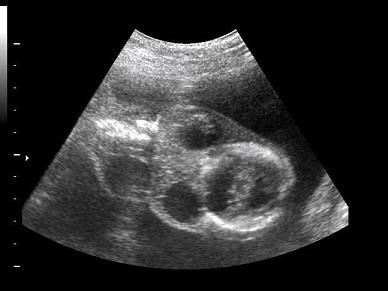

问题 如图,根据胎儿颈部声像图,最可能的诊断是?(?)

选项 A.脊柱裂 B.脑膜膨出 C.淋巴管囊肿 D.单脐动脉 E.正常图像

答案 C